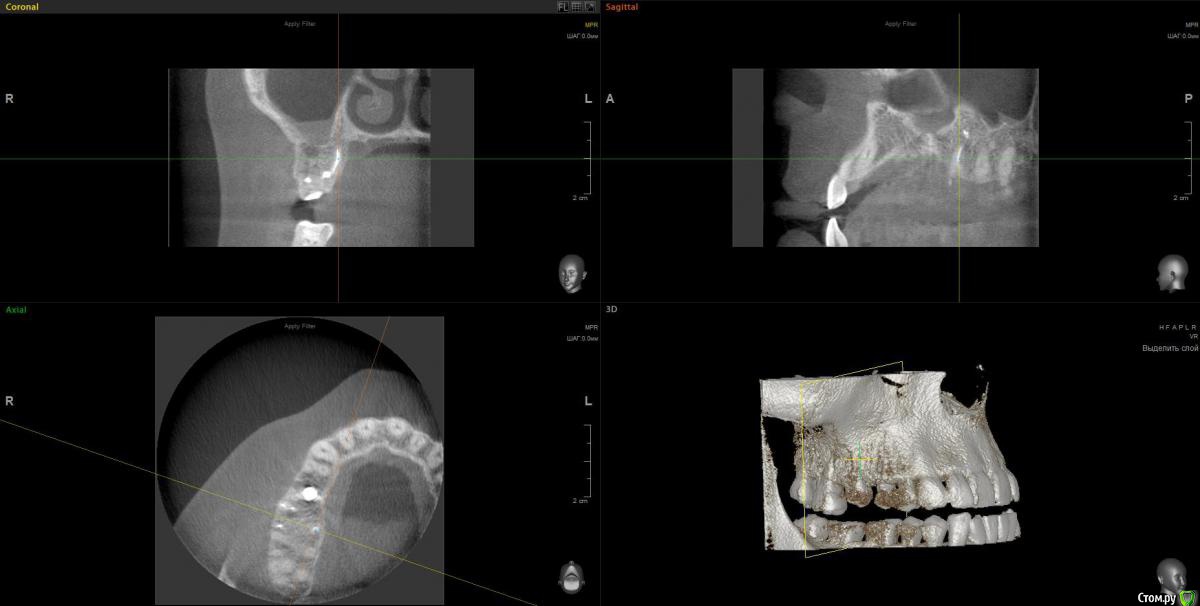

anvladd Опубликовано 31 января, 2017 Поделиться Опубликовано 31 января, 2017 (изменено) Как с носом, не гайморит ли ? 3 d бы глянуть, хотя бы этот сегмент. Изменено 31 января, 2017 пользователем anvladd Ссылка на комментарий

Весна2009 Опубликовано 31 января, 2017 Автор Поделиться Опубликовано 31 января, 2017 Вы тоже думаете, что имплант в гайморовой? Ссылка на комментарий

wladdX Опубликовано 2 февраля, 2017 Поделиться Опубликовано 2 февраля, 2017 Несколько скриншотов на скорую руку. Ссылка на комментарий

Весна2009 Опубликовано 2 февраля, 2017 Автор Поделиться Опубликовано 2 февраля, 2017 Несколько скриншотов на скорую руку.Огромное Вам спасибо! Может быть, есть желающие прокомментировать снимки? Заранее спасибо Ссылка на комментарий